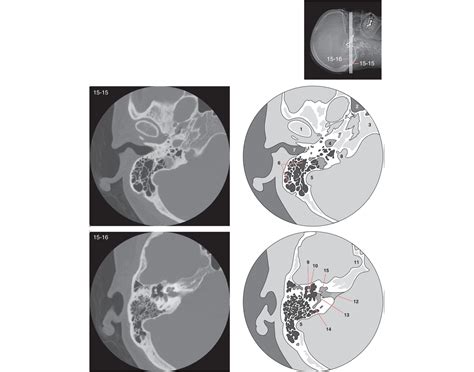

Interpreting Ct Temporal Bone scans requires a keen eye for detail and a thorough understanding of the temporal bone's anatomy. Here are some key points to consider when interpreting these scans:

• Bone Density: Abnormalities in bone density, such as areas of increased or decreased density, can indicate conditions like otosclerosis or infections.

• Fractures: Fractures of the temporal bone can be detected by looking for discontinuities in the bone's structure.

• Erosions: Erosions or destruction of the temporal bone can be seen in conditions like cholesteatoma or mastoiditis.

• Soft Tissue Abnormalities: While CT is primarily used for bony structures, it can also detect soft tissue abnormalities, such as fluid collections or masses.

Radiologists often use a systematic approach to review Ct Temporal Bone scans, starting with the outer ear and progressing inward to the inner ear structures. This ensures that no abnormalities are missed.

Several common findings can be identified in Ct Temporal Bone scans, each with its own clinical significance. Here are some of the most frequently encountered findings:

Finding Description Clinical Significance

Otosclerosis Increased bone density around the oval window Hearing loss

Cholesteatoma Soft tissue mass with bone erosion Potential for hearing loss and facial nerve damage

Mastoiditis Fluid collection and bone erosion in the mastoid air cells Infection and potential for intracranial complications

Facial Nerve Palsy Abnormalities in the facial nerve canal Facial muscle weakness or paralysis

• Cone Beam CT (CBCT): This technique uses a cone-shaped X-ray beam to capture detailed images of the temporal bone. It is particularly useful for evaluating the bony structures in three dimensions.